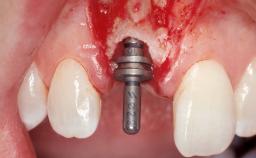

A 30-year-old female patient had lost tooth 21 and was referred to our clinic for consultation and treatment. Due to advanced apical infection, tooth 21 had been extracted two months earlier at another clinic and an acrylic-resin tooth had been bonded to the adjacent teeth. The patient desired implant treatment to avoid any damage to the adjacent natural teeth. While the patient had no history of any systemic disorder, she was a heavy smoker and exhibited medium to advanced periodontitis in the entire jaw. After the initial treatment to achieve a pocket probing depth of less than 4 mm and no bleeding on probing, a decrease in the height of the papillae mesial and distal to the extraction site and overall gingival recession were observed.

Bone Augmentation Horizontal|Staged

Augmentation Materials Autogenous chips|Membrane

Soft Tissue Grafting Simultaneous